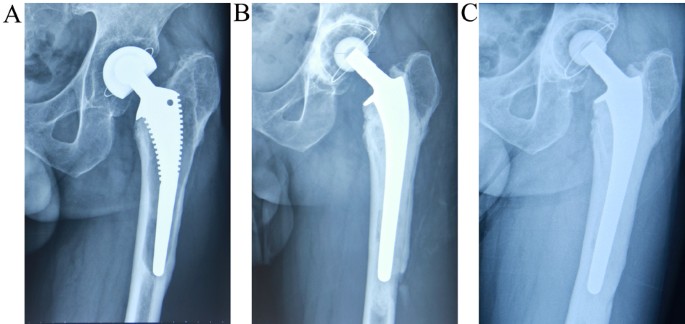

Implants and components used in revision procedures

Revision hip replacement surgery often requires specially designed implants to accommodate the unique challenges that can arise when a hip joint has already been operated on. These challenges may include bone loss, implant loosening, joint instability, or infection. Compared to primary hip replacements, revision implants are typically more robust and versatile, offering added fixation and support where standard implants may no longer be suitable.

Addressing bone loss, instability, and joint integrity

When the bone around the original implant has deteriorated or been damaged, specialised implants can help rebuild structural support. These may include:

- Longer stems to reach deeper into healthy bone and provide a more secure anchor

- Modular components that allow flexibility in tailoring the implant to your individual anatomy and bone quality

- Reinforcement devices or augments to fill bone defects and restore stability

- Dual mobility cups or constrained liners to reduce the risk of dislocation in cases of soft tissue laxity or instability

Professors Hunt and Sallen may also use bone grafts, either from your own body or a donor source, to rebuild areas where bone has been lost.

Careful implant selection for individual needs

At Melbourne Orthopaedic Clinic, your surgeon will thoroughly assess your hip through advanced imaging and clinical evaluation before selecting the most appropriate implant components. Every revision procedure is personalised, with the goal of restoring stability, relieving pain, and supporting long-term joint function.

Before your surgery, your surgeon will carry out a comprehensive assessment to understand why your original implant has failed. This includes reviewing your medical history and ordering diagnostic imaging such as X-rays, CT scans, or MRIs. These help identify issues like loosening, wear, infection, or bone loss. Your surgical plan is then customised to your situation — including the selection of suitable implants, techniques, and contingency strategies for any expected challenges.

After the joint is cleaned and stabilised, the new prosthetic components are carefully positioned. Your surgeon may use cemented or uncemented fixation techniques, depending on bone quality and other individual factors. Advanced alignment and imaging tools are often used during surgery to ensure optimal positioning, joint stability, and limb length restoration.